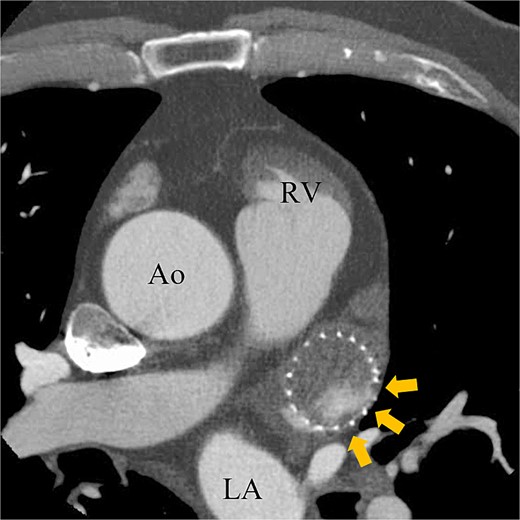

A 74-year-old male with a history of chronic atrial fibrillation (AF) for over 10 years, cardioembolic stroke, and cerebral hemorrhage, who had undergone LAA closure using the WATCHMAN device 1 year prior, was admitted after a follow-up contrast-enhanced CT scan revealed a 25-mm intracardiac mass in the right atrium (RA) (Fig. 1). After the WATCHMAN implantation, the patient was initially on direct oral anticoagulant (DOAC) but switched to dual antiplatelet therapy (DAPT) following the placement of a drug-eluting stent during percutaneous coronary intervention performed 9 months later. Transthoracic echocardiography revealed a left ventricular ejection fraction of 61% and a right atrial mass measuring 17 × 19 mm with slight mobility (Fig. 2). Despite anticoagulation therapy with heparin, the right atrial mass did not reduce in size. The patient decided to undertake surgical removal of the mass due to the potential risks of tumor or embolization. Additionally, contrast-enhanced CT showed a peri-device leak around the WATCHMAN device (Fig. 3). Considering the patient’s history of cerebral hemorrhage and the anticipated future cessation of anticoagulation therapy, we determined to perform WATCHMAN device explantation and LAA closure. Preoperative contrast-enhanced CT showed no thrombi attached to the WATCHMAN device and sufficient distance from the left circumflex artery (LCX) and the device (Fig. 4). We planned to remove the device by incising from the outside surface of the LAA. The Maze procedure was not performed because it was considered less effective due to the patient’s history of AF lasting more than 20 years and the presence of flat f-waves in lead V1 on the 12-lead electrocardiogram.

Preoperative enhanced computed tomography imaging showing the distance between the WATCHMAN device and the LCX was ~9 mm.